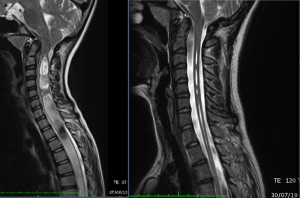

特発性脊柱側弯症

1993年10月20日から2016年11月まで、神経頭蓋脊柱症候群/終糸病によるアーノルド・キアリI型症候群(キアリ奇形I型)、特発性脊髄空洞症、特発性脊柱側弯症の患者さん1000名以上に対して、終糸システム(FILUM SYSTEM®)を適用し終糸切断手術を行ってきました。